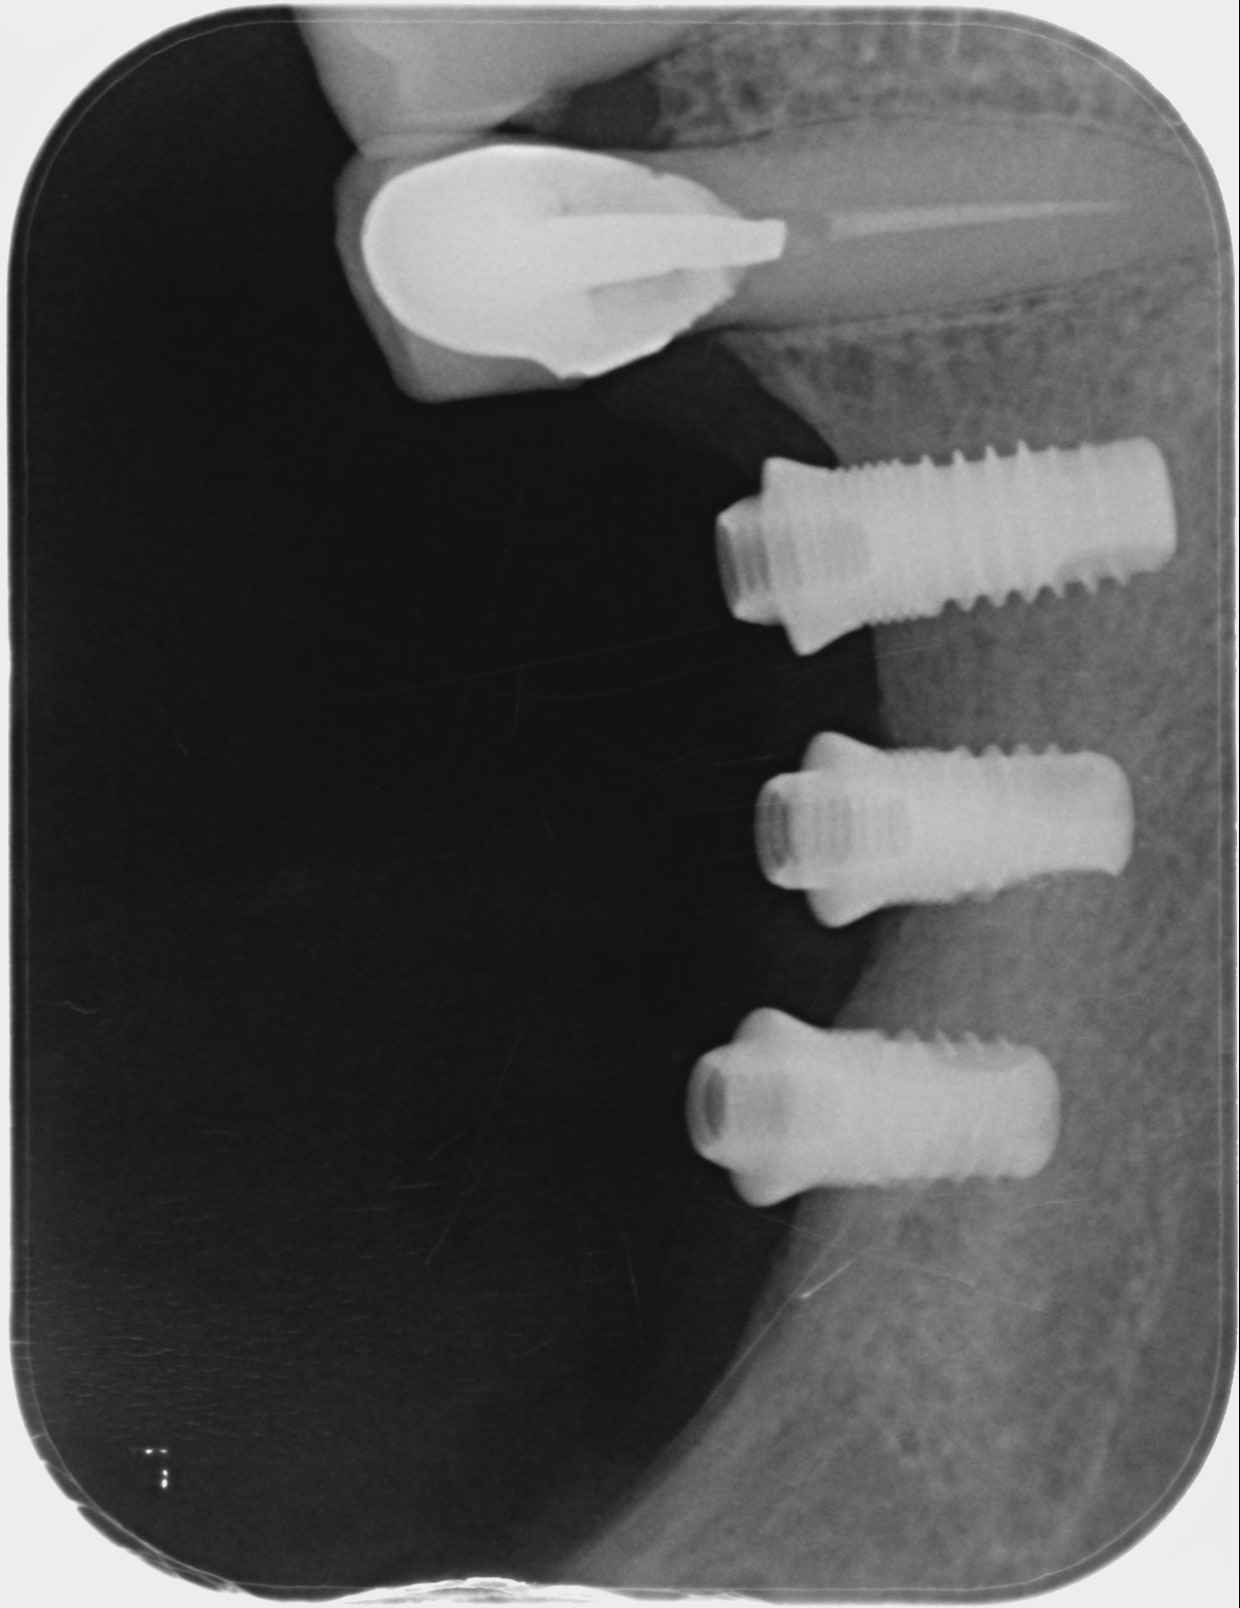

Posés il y a environ 9 ans à Djibouti (militaire par un praticien niçois qui venait faire des vacations)

Bridge s'est dévissé,une vis perdue je voudrais en recommander des neuves et connaitre le couple de serrage.

Empreinte hexagonale compatible avec mon tournevis 3i

Serf EVL compact...maintenant Golbal D

http://osseosource.com/dental-implants/product_info.php?manufacturers_id=92&products_id=729